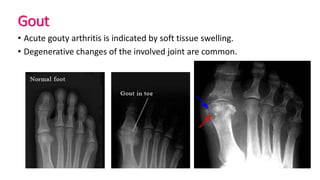

Gout

• Acute gouty arthritis is indicated by soft tissue swelling.

• Degenerative changes of the involved joint are common.